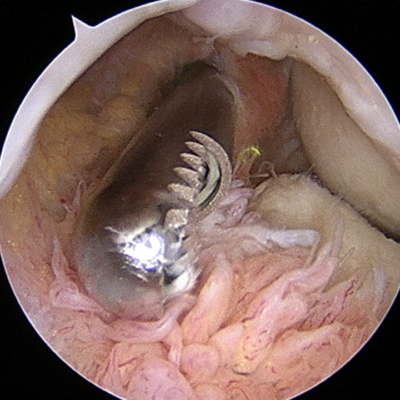

Minimally Invasive Arthroscopy – Small incisions (less than 1cm) for faster recovery and minimal scarring

Common Procedures – Tendon repair (for tennis/golfer's elbow). arthroscopic debridement (for arthritis). fracture fixation. ligament reconstruction (Tommy John surgery). etc.